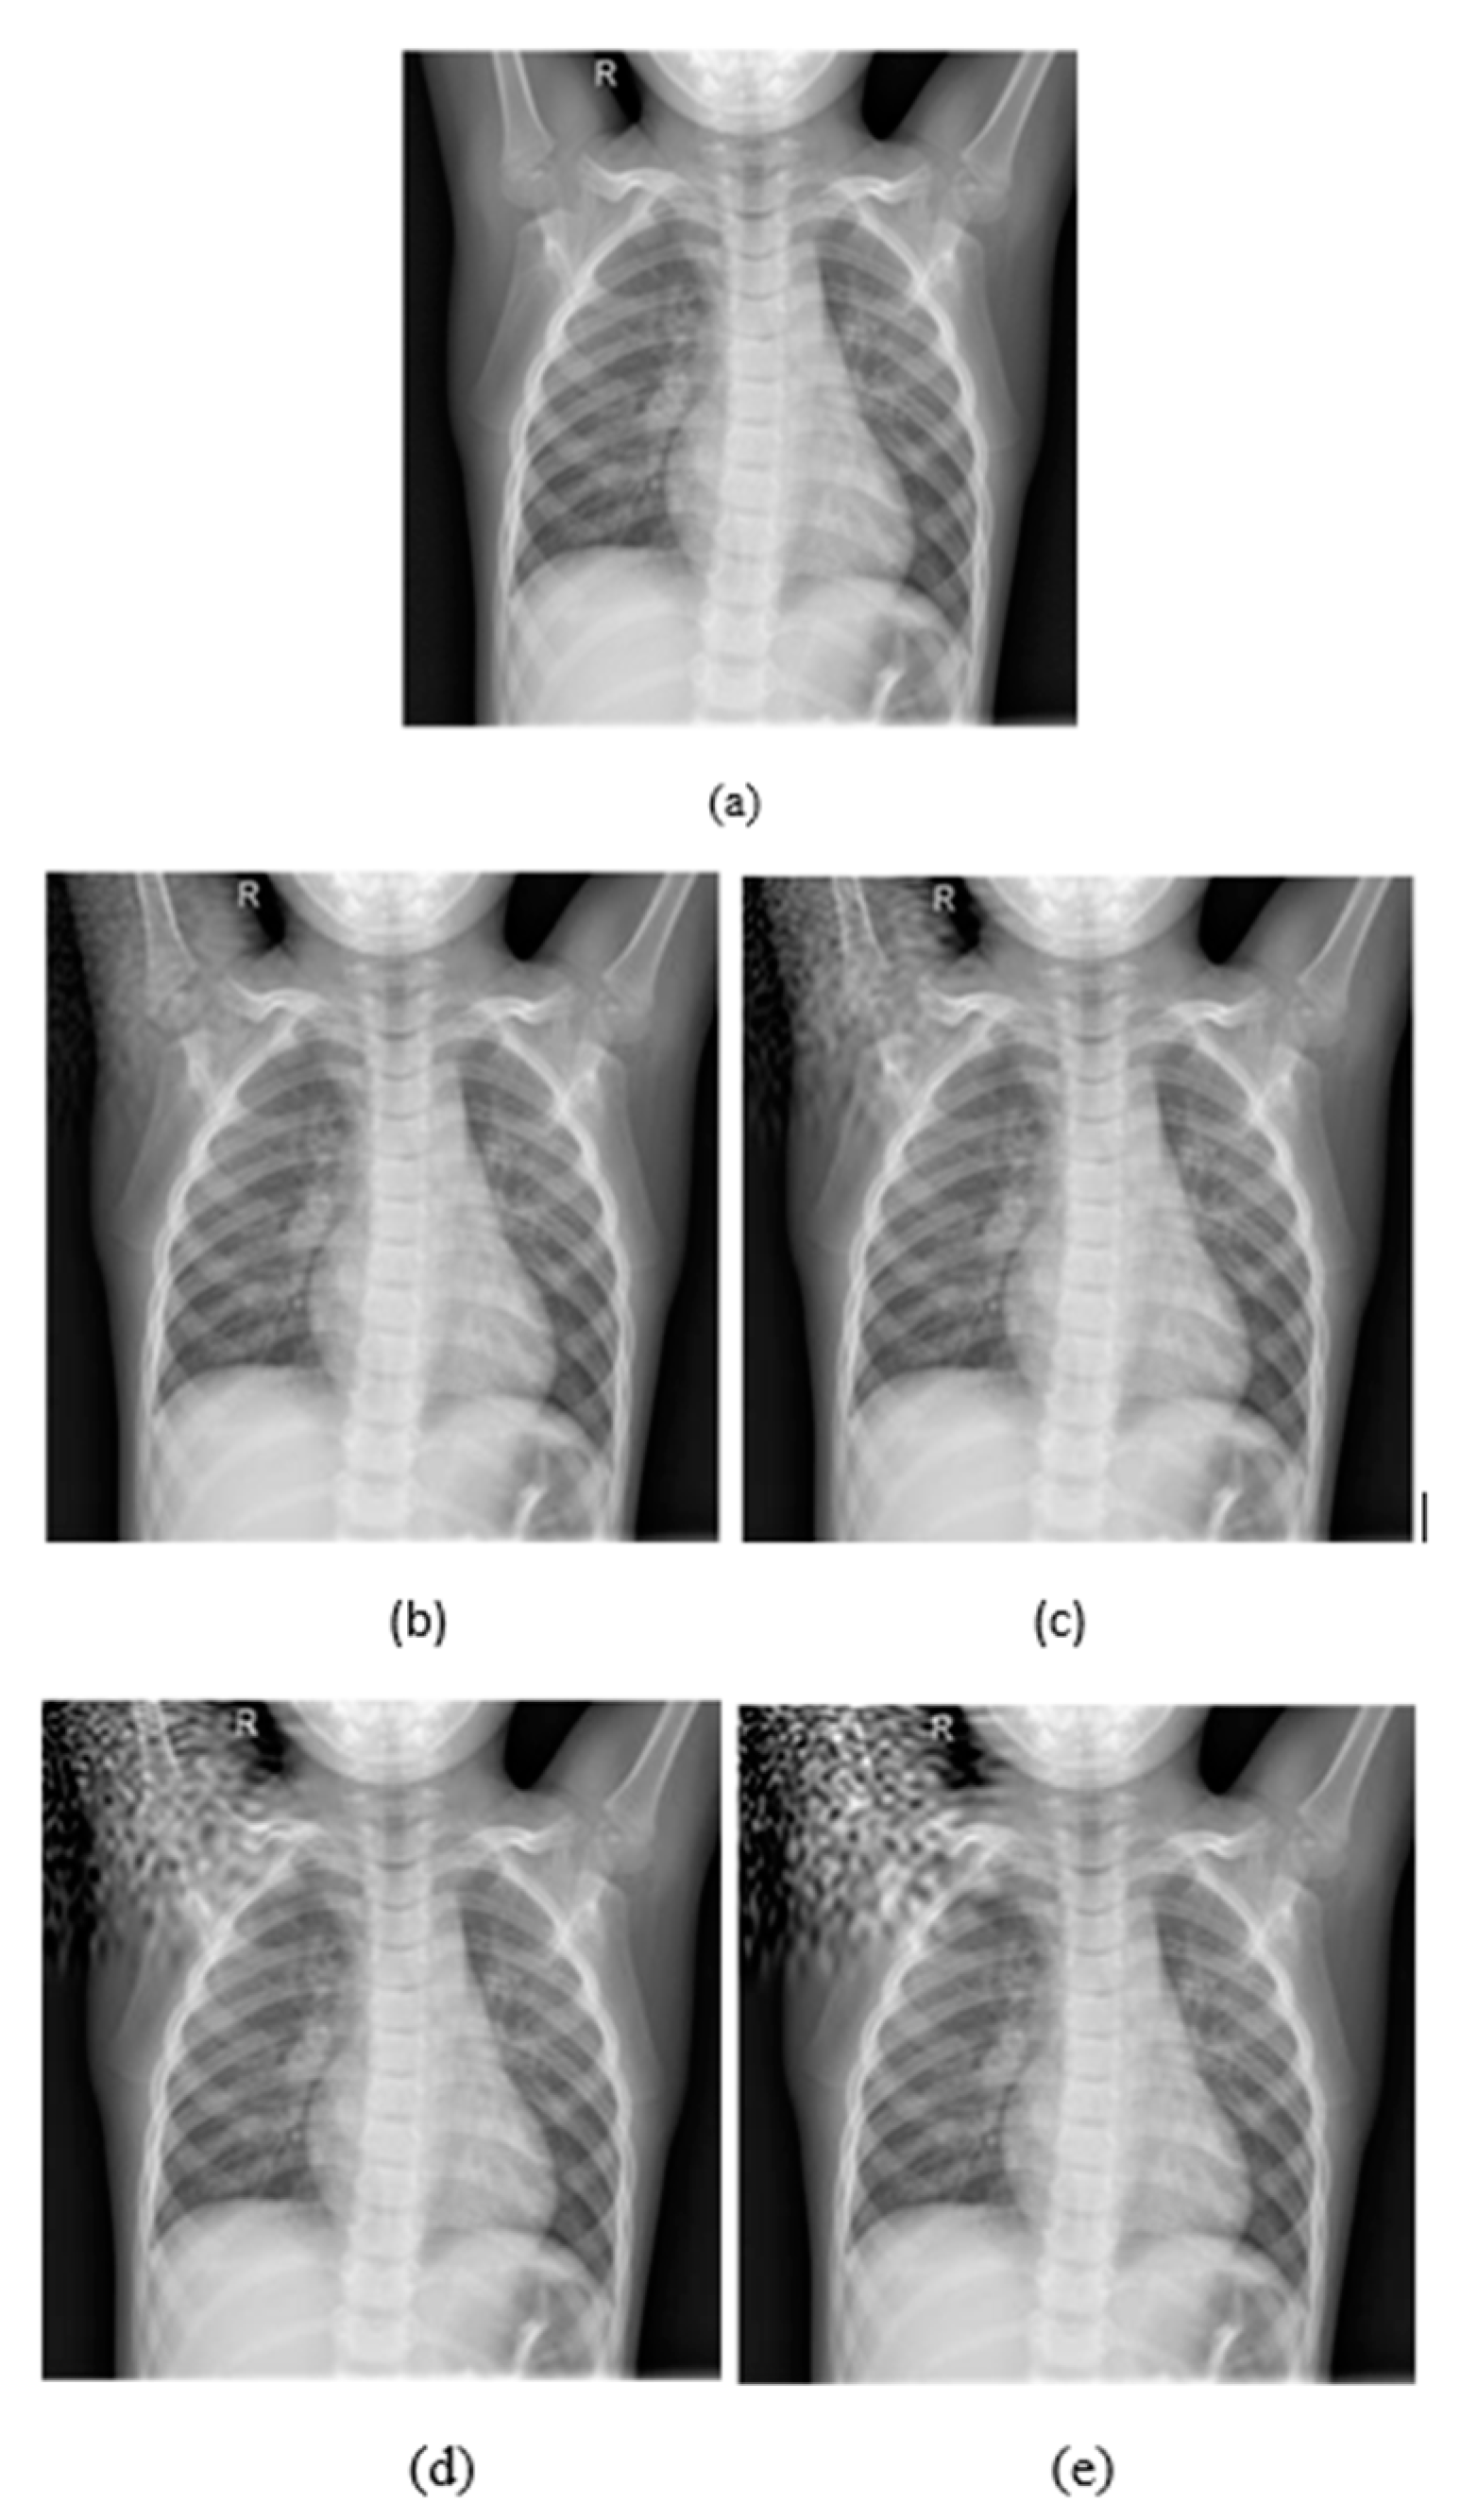

Figure 4.

(a) Initial image. (b) Embedding strength = 50, (c) Embedding strength = 100, (d) Embedding strength = 200, (e) Embedding strength = 300. The rest of the parameters are L-bit = 1000, p1 = 0.1, p2 = 0.1.

As it is depicted in Figure 4, increasing the embedding strength the quality of the image is getting worse and the noise becomes more perceptible and intense. On the other hand, in Figure 5 the intense of the noise is almost the same in all L-Bit lengths, but it changes the magnitude of the noise.